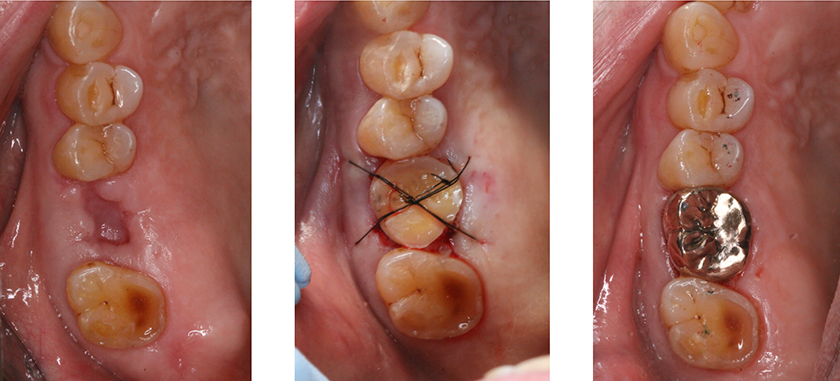

【術前口腔内写真】

右下の第2大臼歯の被せ物を除去したところ。

虫歯が進行し、保存は困難です。

まず、右下第2大臼歯を抜歯しました。

上顎の親知らずを先ほど第2大臼歯を抜歯したところに移植しました。